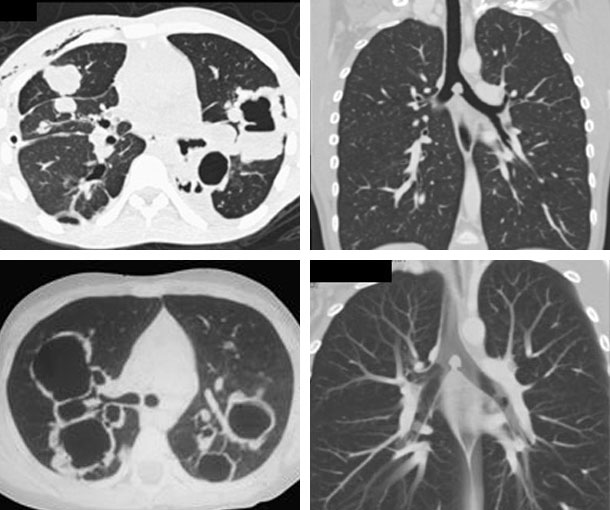

Chest CT Appearances

Laryngotracheobronchial Papillomatosis CT Findings

- Focal or diffuse airway narrowing

- Nodular lesions that can be pedunculated or sessile

- Polypoid lesions

- Most typically seen in the larynx but can affect any part of the tracheobronchial tree